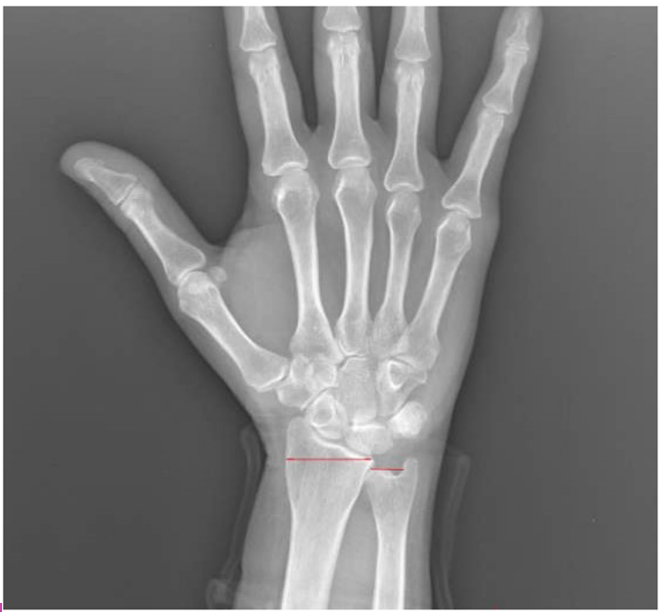

The radius and ulna are connected by the dorsal and volar radioulnar ligaments and are expected to be in a neutral position relative to each other within the wrist joint.[4] Ulnar variance is a term used to describe the positional relationship between the distal ulna and radius. Negative ulnar variance is the presence of the ulna 1 mm or more proximal to the radius and has been associated with conditions such as ulnar impingement syndrome, scapholunate dissociation, and Kienböck’s disease (Figure 1). Positive ulnar variance is the presence of the ulna 1 mm or more distal to the radius and is associated with conditions such as ulnar impaction syndrome, cartilaginous tears in the carpal bones, early degenerative changes, and triangular fibrocartilaginous complex (TFCC) tear (Figure 2).[5]

Hand and wrist radiographs were evaluated blindly by 2 rheumatologists (MP-SK). Hand radiographs were analyzed according to the Modified Sharp Score (MSS) system.7 The presence of any erosion or joint space narrowing (JSN) was used as a criterion to define “RA-type joint involvement (RJI).” “Severe joint involvement (SJI)” was defined as the presence of erosion with a score of 3 or higher or JSN with a score of 4 or more according to the MSS. Patients were also evaluated for ankylosis of any hand joint. Ulnar variance, as described by Hulten, was determined by measuring the distance between horizontal lines drawn at the subchondral bone of the distal radius, just beneath the articular cartilage, and the most distal subchondral border of the ulnar head.[8] A displacement of 1 mm or more of the ulna relative to the radius was defined as AUV. Radiographic evaluation was performed with full agreement; if there was disagreement between the readers, the X-ray was re-evaluated and an agreed final decision was made.